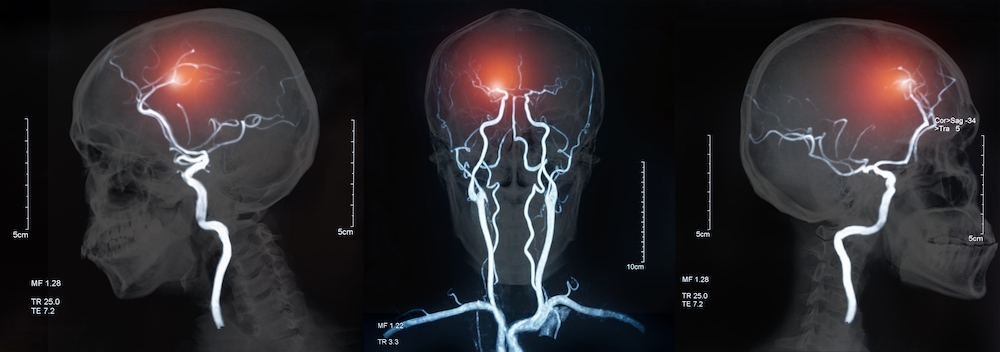

Lacunar strokes affect at least 25,000 people in the UK each year. They’re thought to be caused by cerebral small vessel disease (cSVD), where small blood vessels deep within the brain become damaged and stop working properly. Lacunar strokes can have distressing effects as people may develop problems with their thinking and memory, movement, and even dementia. There are currently no effective treatments.

Banner image: Shutterstock/create jobs 51